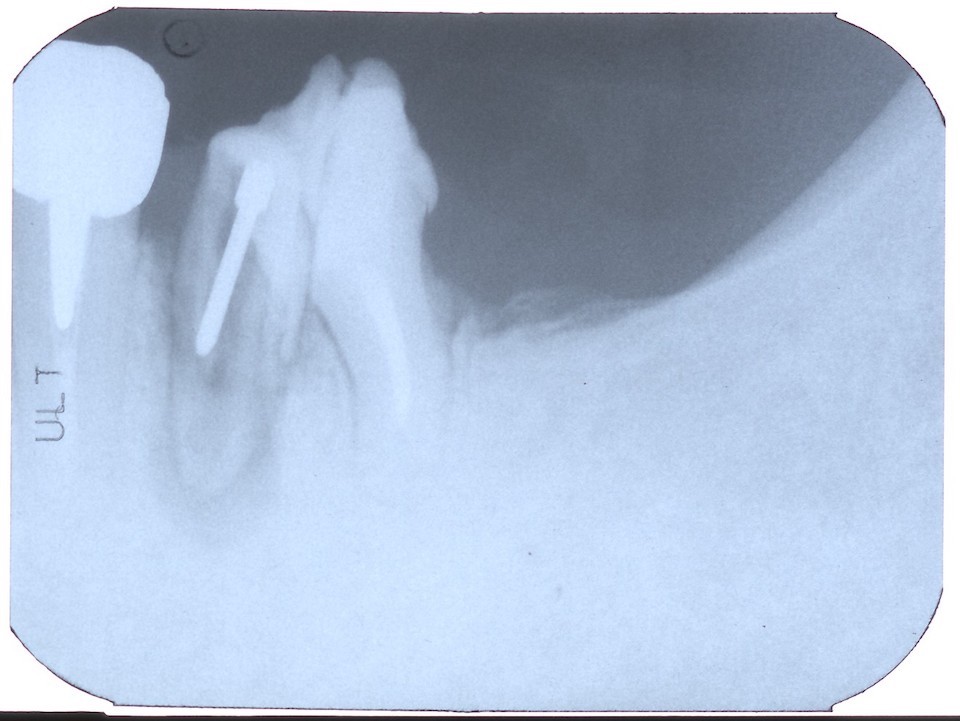

今日の抜歯再植術シリーズ39.1 2025.11.14

今日の抜歯再植術シリーズ39.0 2025.11.13

今日の抜歯再植術シリーズ38.3 2025.10.14